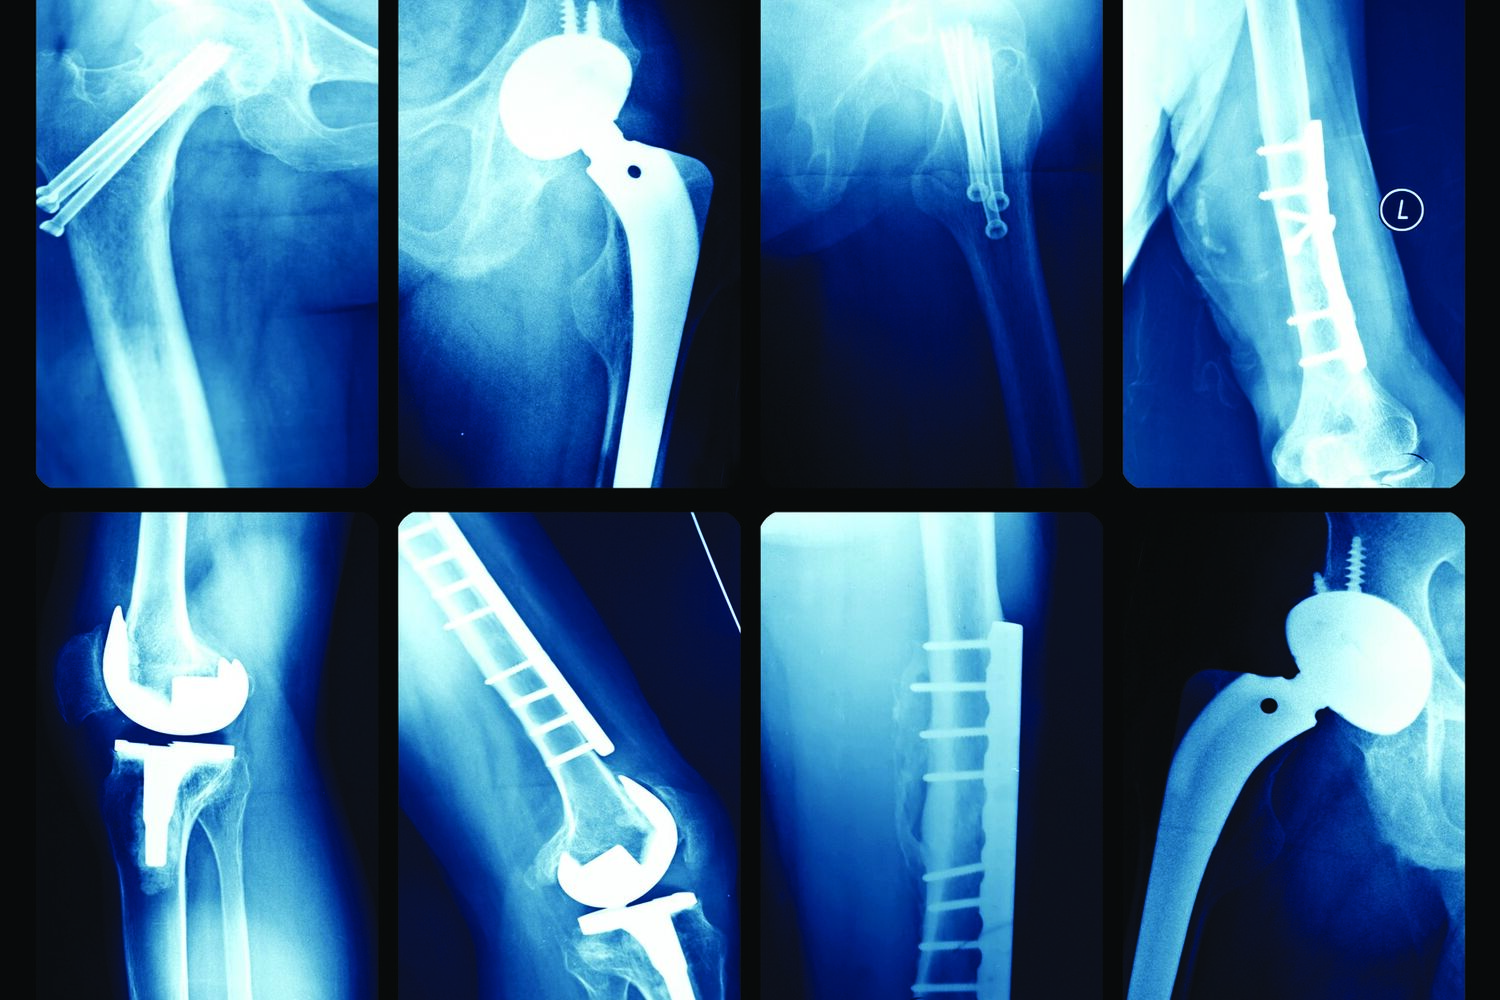

As infeções osteoarticulares, ou seja, dos ossos e das articulações, em particular, têm um significativo impacto negativo não só em termos médicos, com enorme morbilidade e mesmo mortalidade, como em termos sociais e económicos, com custos excessivos que derivam da necessidade de múltiplas cirurgias, internamentos e tratamentos antibióticos prolongados. Com o aumento consistente do número de próteses realizadas anualmente, e um número cada vez maior de pessoas a viver com alguma prótese, as estatísticas nacionais e mundiais apontam para um crescimento exponencial futuro das infeções após artroplastias.

A particular dificuldade no combate às infeções osteoarticulares prende-se com as especificações que lhes são inerentes. Por um lado, o seu diagnóstico é frequentemente difícil, pois muitas vezes a infeção não é evidente: repetidamente não estão presentes os tradicionais sinais clínicos de infeção e esta traduz-se “apenas” em dor persistente e falência inexplicada de sucessivas cirurgias de revisão. Por outro lado, mesmo após a determinação do diagnóstico, o tratamento é exigente e laborioso, comummente associado a taxas de falência elevadas que potenciam as consequências adversas.